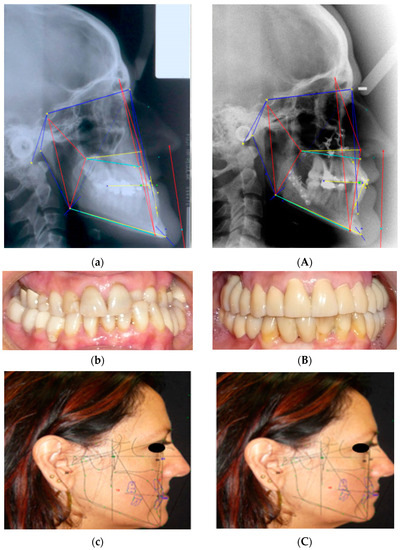

For each case, instrumental evaluations are performed: orthopanoramics (OPT), Latero-Lateral (LL) and Antero-Posterior (AP) teleradiographs, 3D Cone Beam CT (CBCT). More specifically, the CBCT scans were performed both with and without the diagnostic prostheses: this was done to allow for the 3D evaluation of the relationship between the prostheses and the skeletal bases before the surgical phase (if necessary). Lastly, a CT of the condyles in both open and closed positions was performed. VTO and cephalometric analysis are always performed before and after surgery [29,30] (Figure 3). The preliminary study and design phase was carried out digitally using 3D software (Dolphin Orthodontics software) while the fixed prosthetic rehabilitation using optical impressions (digital scanner) and CAD/CAM equipment. The surgical phase, on the other hand, was carried out according to traditional techniques.

Figure 3.

VTO and cephalometric analysis: N—nasion; S—sella; Po—porion; Or—Orbital point; CC—craniocranical point; Ba—basion; A—subspinal point; B—supramental point; Pg—pogonion. Different color lines have been used to make the image easier to read.

A 45-year female patient with III dento-skeletal malocclusion, bilateral cross-bite, and TMJ’s dysfunction: VTO and intraoral views before (a–c) and after orthodontic surgery and new prosthetic rehabilitation (A–C). Different colored lines were used to facilitate comparison between the two pre- and post-treatment images.

Figure 6.